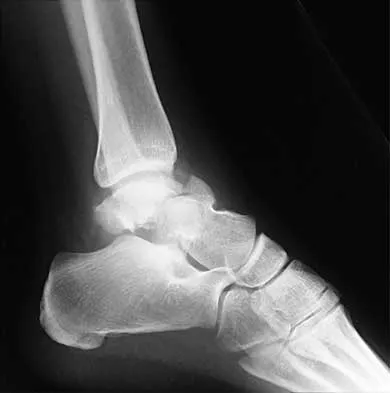

Figures 4a through 4c show the radiographs of a 43-year-old woman who sustained a twisting injury to her right ankle. She has ankle pain and tenderness medially and laterally. To help determine the optimal treatment, an external rotation stress radiograph of the ankle is obtained. This test is designed to evaluate the integrity of what structure?

Explanation

In the presence of a supination external rotation-type fracture of the distal fibula (Weber type B), stability of the ankle is best assessed by performing an external rotation stress AP view of the ankle. This test is used to assess the integrity of the deltoid ligament. The presence of a deltoid ligament rupture results in instability and generally is best managed surgically. The gravity stress test can also be used. Egol KA, Amirtharajah M, Tejwani NC, et al: Ankle stress test for predicting the need for surgical fixation of isolated fibular fractures. J Bone Joint Surg Am 2004;86:2393-2398. McConnell T, Creevy W, Tornetta P III: Stress examination of supination external rotation-type fibular fractures. J Bone Joint Surg Am 2004;86:2171-2178.